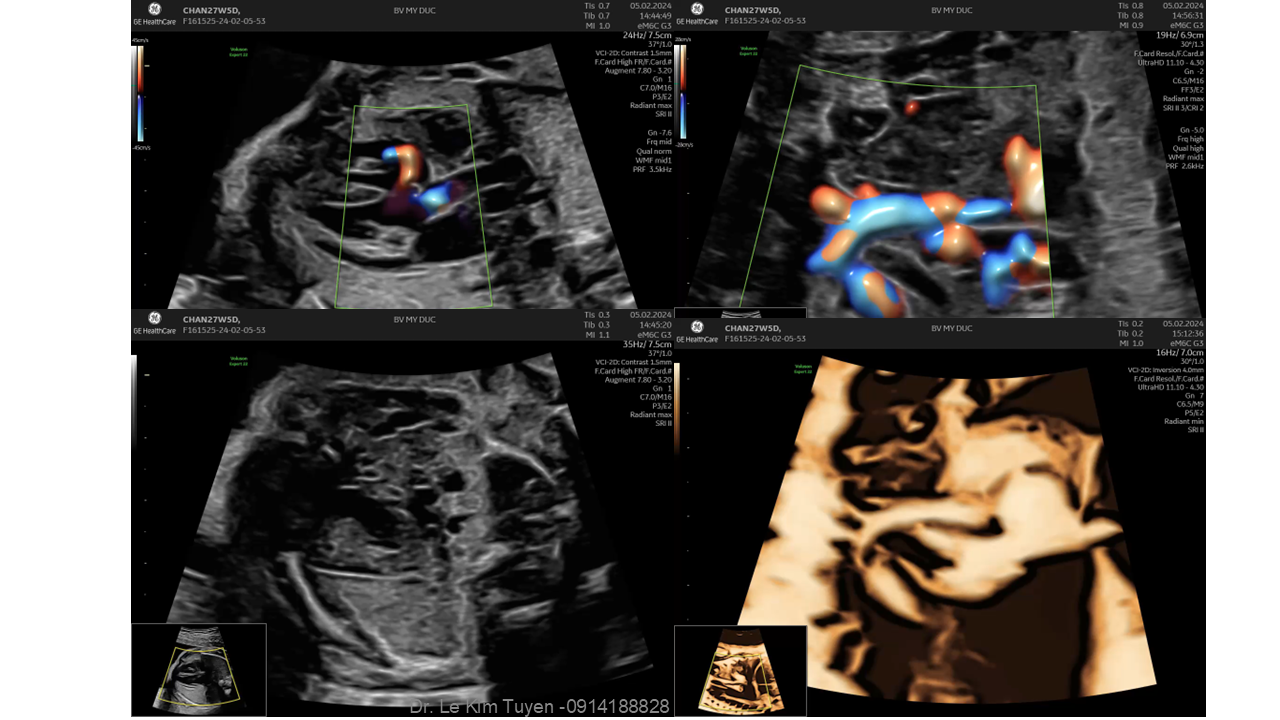

Áp dụng công nghệ Graphicflow trong phát hiện bệnh tim bẩm sinh cần cấp cứu sơ sinh

TS. BS. Lê Kim Tuyến

Bệnh viện Tim Tâm Đức